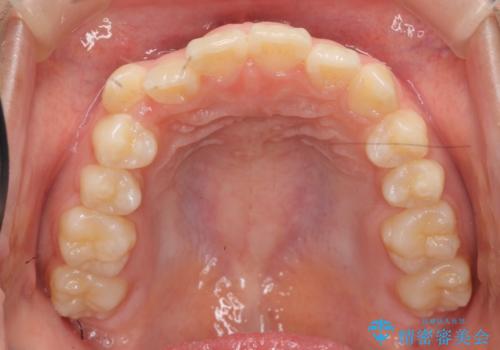

インビザラインで行う八重歯の治療

- 笑った時に目立つ八重歯の矯正治療を求めて来院されました。

マイクロインプラントを用いた臼歯の後方牽引、およびゴムかけ等の付加処置を駆使して八重歯の治療を行っていきます。

しっかりとゴムかけを頑張っていただいたおかげで、上顎臼歯の後方移動が達成されしっかりとした噛み合わせの構築と、八重歯の治療を達成することができました。